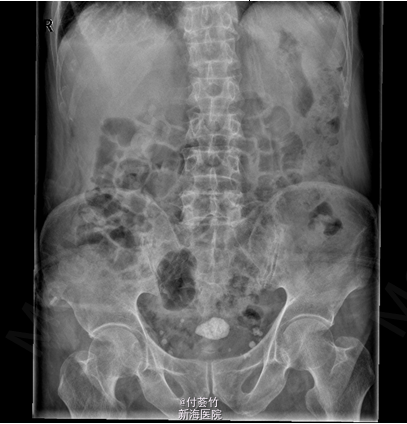

患者,男性,82岁。患者于2月前无明显诱因出现尿频,尿急,排尿结束时尿痛夜尿次数增多,排尿迟缓,尿流断续、变细,射程变短,无尿急、尿痛,无肉眼血尿、尿道口流脓,无腹痛、腰痛,未予特殊处理。外院B超提示膀胱结石;前列腺稍大。现为进一步诊治收入我科。

双肾区无红肿、隆起,无叩痛,双侧肋脊点、肋腰点无压痛。腹平软,双侧上中输尿管点无压痛,膀胱区无压痛。双侧腹股沟区未触及肿物 入院后查双肾CTU:膀胱结石,慢性膀胱炎,膀胱少许积气;左肾下部病灶,考虑良性病变,复杂囊肿可能大;双肾多发囊肿;前列腺电切术后改变,残留前列腺钙化